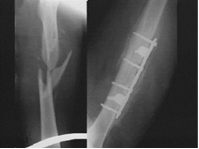

Оперативное лечение. Наиболее распространённым методом оперативного лечения перелома диафиза бедра является интрамедуллярный остеосинтез металлическим штифтом. При этом чаще пользуются ретроградным методом его введения. Другим методом является экстрамедуллярный остеосинтез массивными компрессирующими пластинами.

При данном типе травмы изначально методом лечения использовалось скелетное вытяжение, затем было произведено оперативное лечение: закрытая репозиция, интрамедуллярный МОС с блокированием перелома правого бедра с рассверливанием костномозгового канала.